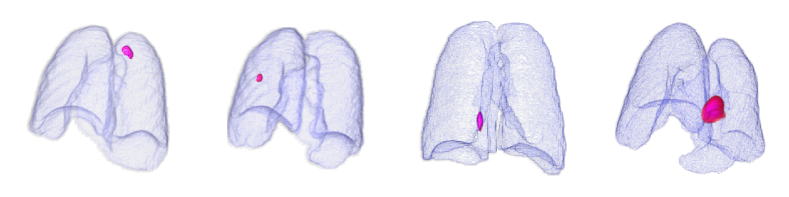

Finally, we evaluated the 3D abnormal (lesion) localization performance of the proposed VMPR-UAD. Of the 63 cancer cases in the MSD dataset with ground-truth annotations available, we excluded two cases (cases 38 and 96) of incorrect annotation or showing other diseases. We calculated whether the cancer area predicted by VMPR-UAD (binarized at a certain high-probability threshold) overlapped with the annotated cancer area. As a result, 57 of the 61 cases showed overlapping, demonstrating that VMPR-UAD can localize 3D lung anomalies (cancer in this case) with an accuracy of 93. Some localization examples in 3D data are shown in Fig. L. The red points in Fig. L(b) show the 3D cancer locations that the proposed method estimates with the highest confidence (i.e., location of highest pixel value in the 3D anomaly map). The red points in Fig. L(a) show the ground-truth cancer location. The ground truth and prediction shown in Fig. L confirm that VMPR-UAD correctly finds the lung anomaly 3D region. More detailed visualization results are available in the Supplementary Material. The prediction consistency can also be observed in 2D slices, as shown in Fig. M, where our anomaly localization map indicates correct cancer regions. Hence, the proposed VMPR-UAD can automatically localize or segment lesions without requiring any lesion information (i.e., using only CT slices from healthy subjects) for training.